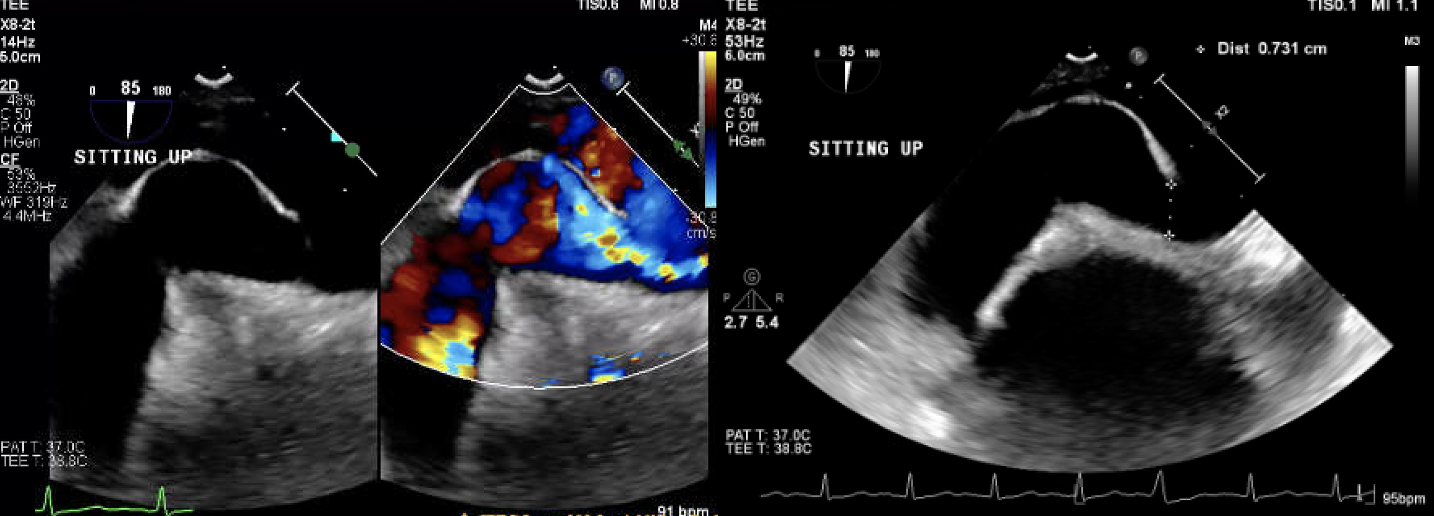

A 78-year-old man with a history of Parkinson’s, TIAs, and scoliosis presented with a sequalae of symptoms concerning for recurrent TIA, however extensive workup demonstrated no evidence of acute intracranial abnormalities. Subsequently, he developed acute hypoxic respiratory failure requiring high-flow nasal cannula. Initial chest CT angiography (CTA) and X-ray were negative for acute pulmonary pathology. A transthoracic echocardiogram (TTE) with bubble study was positive for moderate right-to-left shunt through a patent foramen ovale (PFO). Subsequent imaging modalities, including right heart catheterization, transesophageal echocardiography (TEE) with bubble study, cardiac CT, and cardiac MRI, exhibited normal hemodynamics, positive PFO with left-to-right shunt, and no evidence of significant right-to-left shunt (normal Qp:Qs). Of note, he was discovered to have significant hypoxia while sitting up but remained on room air while supine. In order to evaluate for platypnea-orthodeoxia syndrome (POS), TTE with agitated saline contrast was performed which was grossly positive after 5 cardiac cycles while in the supine position and 3 cardiac cycles while upright, raising concern for pulmonary arteriovenous malformations (AVMs). However, repeat CTA was negative for pulmonary AVMs. Finally, repeat TEE bubble study was performed while the patient was supine (Images A) and sitting up (Images B) which demonstrated a PFO with bidirectional shunting. While the patient was sitting up (Images B), there was stretching of the PFO with significant, continuous right-to-left shunting likely precipitated by the patient’s significant scoliosis. The patient underwent successful percutaneous PFO closure (Images C), which immediately resolved his hypoxia.